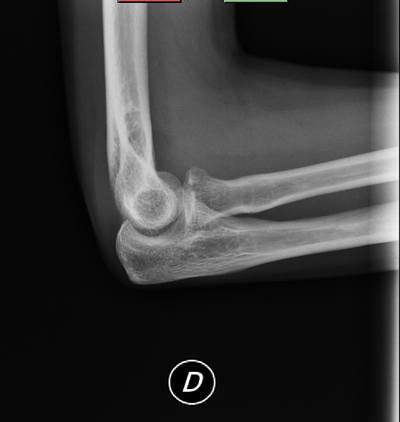

En RX simple no se aprecian claras líneas de fractura (figura 1 y figura 2), y ante la duda se decide realizar proyecciones adicionales para intentar despejar cabeza de radio. Se realizan dos proyecciones adicionales: oblicua de codo (oblicuando todo el cuerpo del paciente, para no movilizar el codo por dolor), y perfil de codo angulado el tubo caudalmente entre 10-15 grados. En ambas proyecciones se visualiza una clara fractura del mismo (figura 3 y figura 4).

(figura 1)